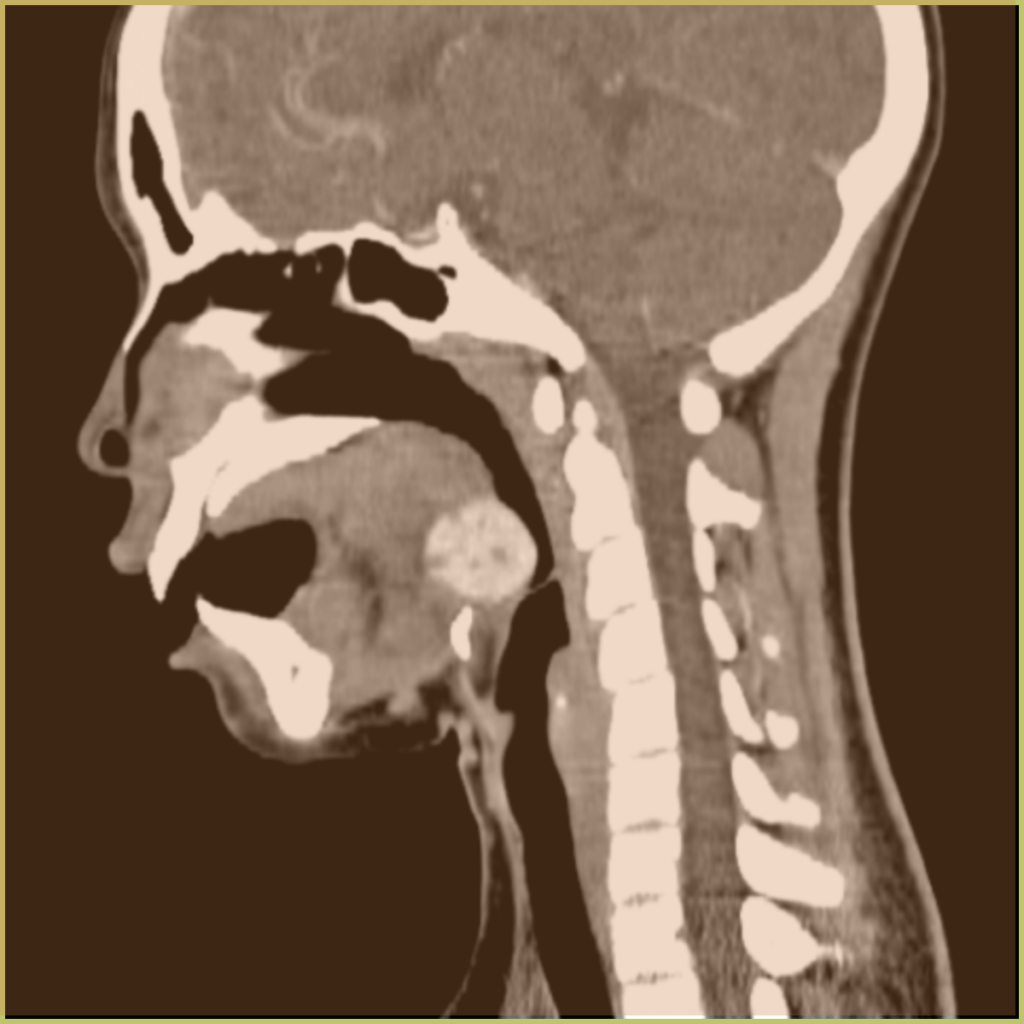

Lingual Thyroid is a rare lesion in the oropharyngeal region caused by the failure of thyroid primordium to descend from the foramen cecum into the anterior neck. This results in thyroid tissue seen within the tongue. The exact mechanism is unclear. The common clinical presentation includes:

- Dark well vascularized mass on the midline of the tongue around the foramen cecum.

- May interfere with swallowing and breathing in infancy.

- Bleeding may occur.